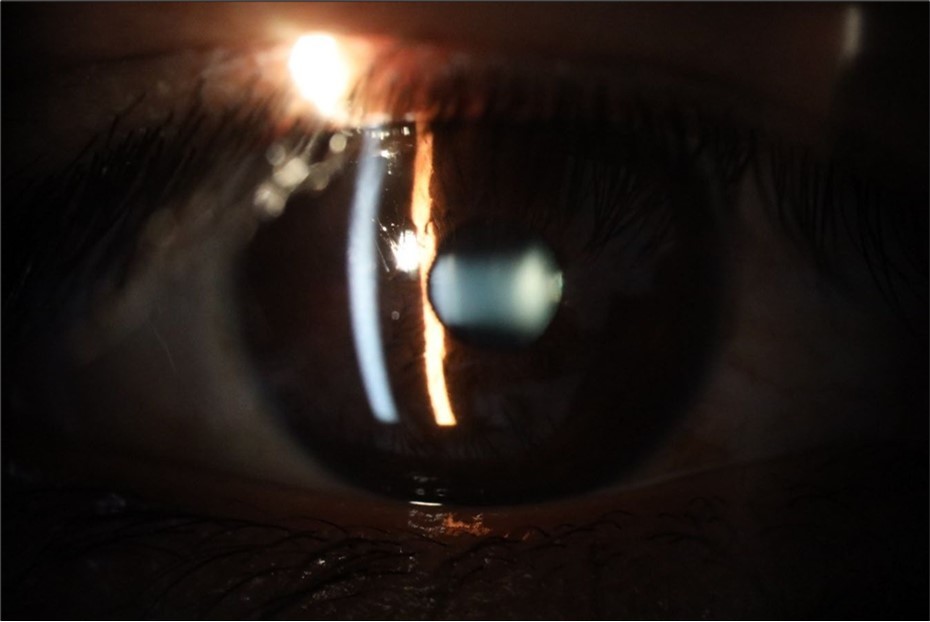

Figure 28.The photograph of the left eye shows a specular reflection without pathology data.

Figure 29.The transparent media of the left eye does not show any alteration.